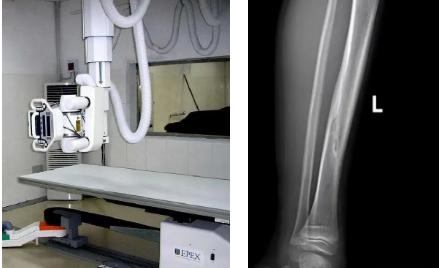

一般骨科創(chuàng)傷的病人,只要到影像科拍一張X光片,很快就會明確診斷有沒有骨折。然而有一些特殊類型骨折的病人,由于拍片影像重疊的緣故,或者骨折未發(fā)生明顯移位,病變可能顯示不出來,等過了一段時間后,骨折部位才能夠顯示清楚。這種類型的骨折,叫做隱匿性骨折。若在臨床上診斷及時且明確,及時固定患者的骨折部位,進行適當(dāng)治療并減少運動,對患者的恢復(fù)有重要意義。

1.定期復(fù)查。一般于骨折后2-4周,骨折進入骨痂期,骨折斷端有新生骨形成,呈明顯高密度,無論是X線或是CT,都能比較清晰觀察到,通過前后圖像對比,較容易診斷隱匿性骨折。